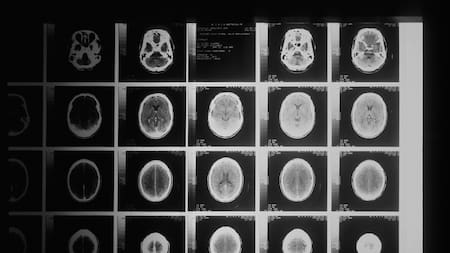

Cerebro. Foto: Unsplash.